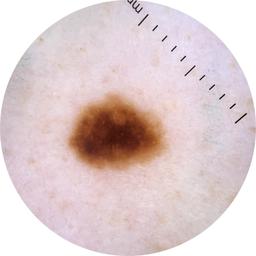

MEL-SELF - Dermoscopic

- Name: MEL-SELF - Dermoscopic

Description:

Dermoscopic lesion images (close-up views of benign and malignant lesions) from the MEL-SELF trial (the Melanoma Self Surveillance trial).